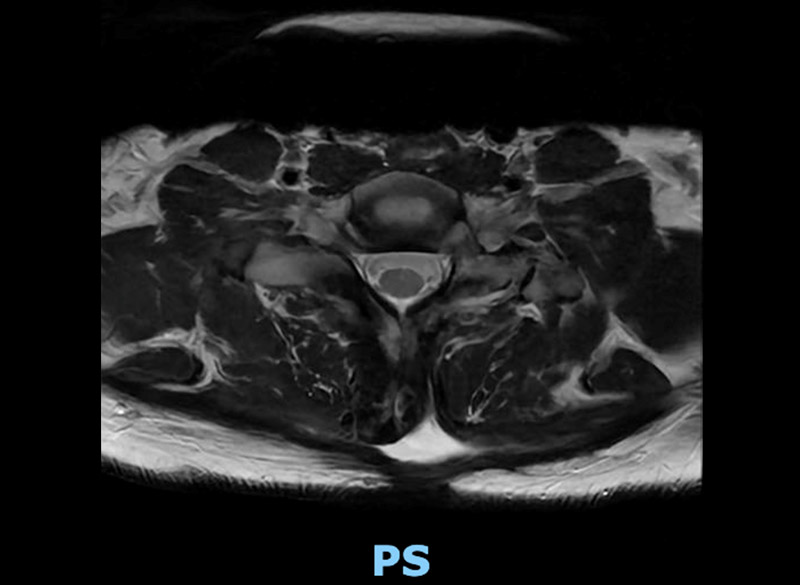

Postop axial mri

Postop axial MRI at C7-T1 showing no more infection and symmetric CSF space around the spinal cord, which has reassumed its oval shape now that it’s no longer compressed.